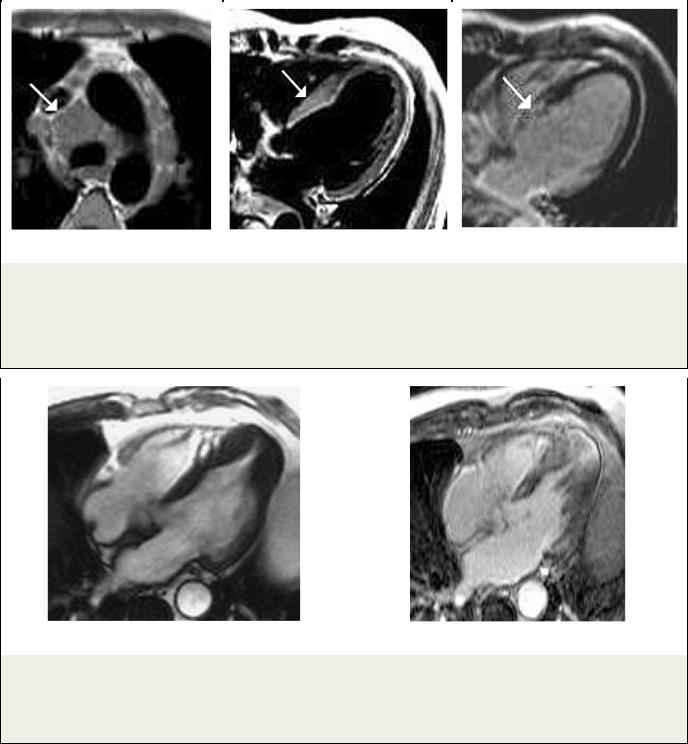

Рис. 5. МРТ сердца.

Пациент К., саркоидоз; а – Т1-ВИ; увеличенные лимфоузлы в средостении (стрелка); б – Т2-ВИ; МЖП утолщена в базальном сегменте (стрелка) и интенсивность МР-сигнала повышена от утолщенного участка, что позволяет говорить об остром поражении; в – Томограмма с отсроченным контрастированием, видна зона накопления КС в утолщенном сегменте МЖП (стрелка).

Рис. 6. МРТ сердца.

Четырехкамерная длинная ось ЛЖ. Пациент С., апикальная ГКМП; а – Кино-МРТ, утолщение апикальных сегментов МЖП и боковой стенки; б – Отсроченное контрастирование. Видны множественные участки контрастирования в гипертрофированных сегментах.